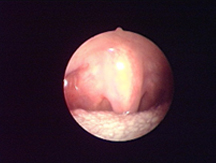

經(jīng)典案例

手術(shù)圖片